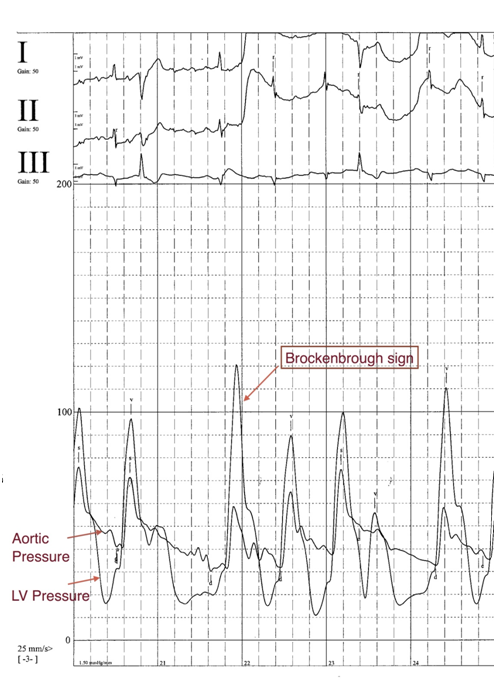

An 80-year-old woman with a history of revascularized coronary artery disease (CAD) and Parkinson’s Disease presented with episodic dizziness and left sided chest pressure that occurs when climbing one flight of stairs. Her symptoms resolve only after lying supine at the top of the stairs. Changes in vital signs taken at the bottom of and after climbing one flight of stairs were: systolic blood pressure (SBP): 132 to 82mmHg; heart rate: 70 to 92 beats per minute (bpm). She did not develop symptoms when walking on a treadmill without an incline for 30 minutes. Her medications include metoprolol XL 50mg daily and Carbidopa/levodopa 25/100mg twice daily. On exam, moving from a supine to a standing position was associated with chest pain, orthostasis (a 36mmHg decrease in SBP) and development of a systolic ejection murmur heard loudest at the left sternal border. She was initially treated with midodrine, which was not associated with a significant change in her symptomatology. A tread mill sestamibi stress test was negative for ischemia. Echocardiography demonstrated a small left ventricular (LV) cavity with hypertrophy and hyperdynamic systolic function. Valsalva maneuver was associated with a 49mmHg gradient across the left ventricular outflow tract (LVOT). Diagnostic cardiac catheterization revealed widely patent stents and no obstructive CAD. No significant LVOT gradient was noted at rest. A single dose of intravenous hydralazine was administered to treat hypertension during the catheterization procedure. This resulted in systemic hypotension, which was associated with the development of chest pain and an LV-aortic gradient of 60mmHg with a Brockenbrough sign (Figure 1). As a result of these findings, her Carbidopa/levodopa dose was decreased to treat her orthostatic hypotension. On subsequent follow-up, her orthostatic hypotension improved and she reported significant improvement in lightheadedness, chest pain, and ability to walk stairs without symptoms.

Figure 1 Diagnostic cardiac catheterization showing left ventricular gradient of 60mmHg with Brockenbrough sign exacerbated by systemic hypotension after hydralazine administration.